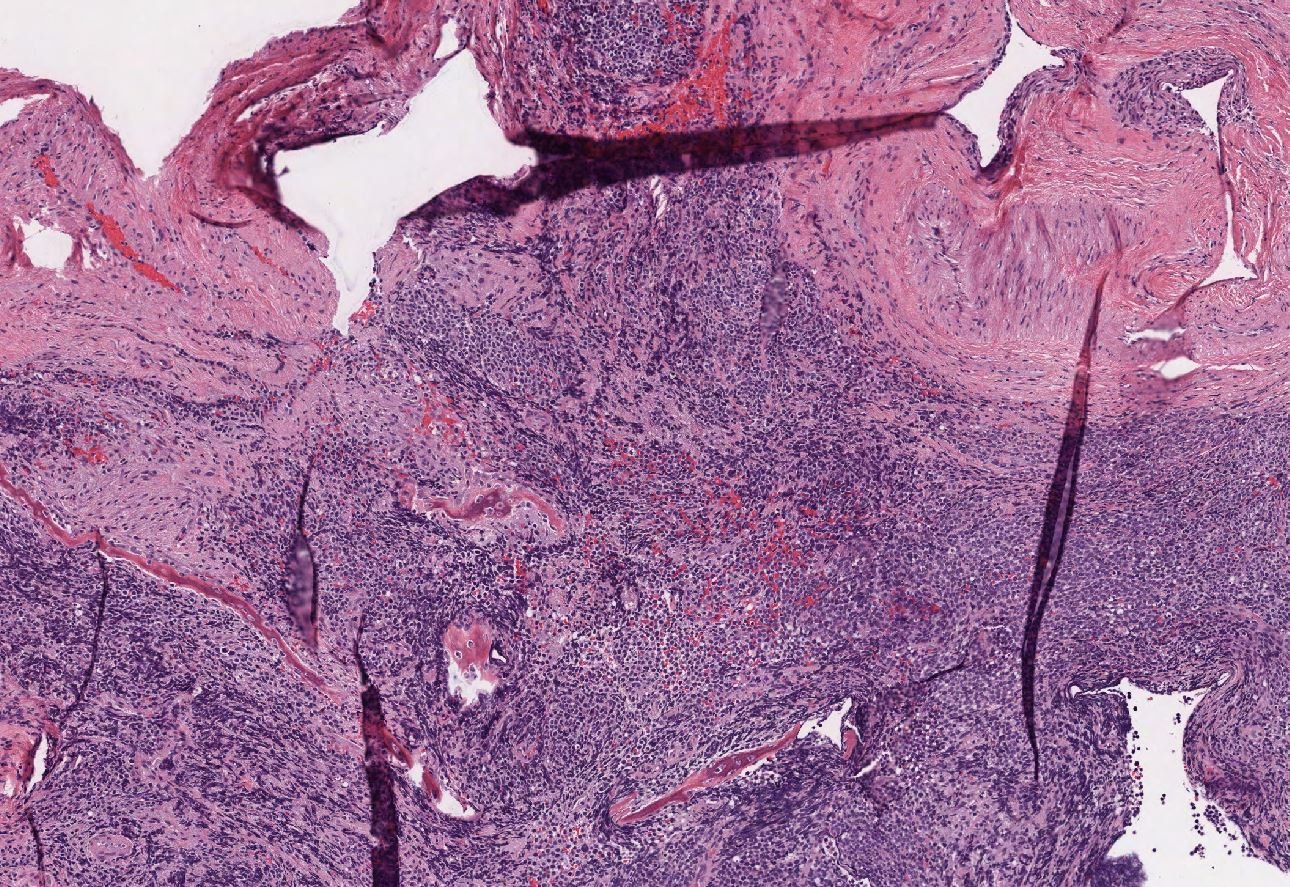

Case: MaxillaryMass

Specials to Order:

Final Diagnosis: